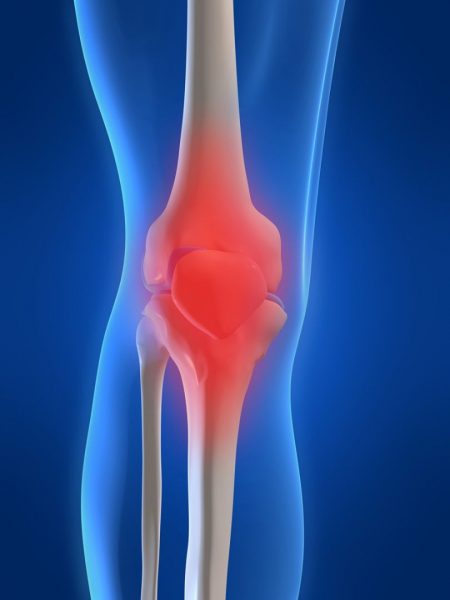

Ако ве мачат болки во зглобовите, имате чувство на “тежина” во нозете, стари повреди, итн.…